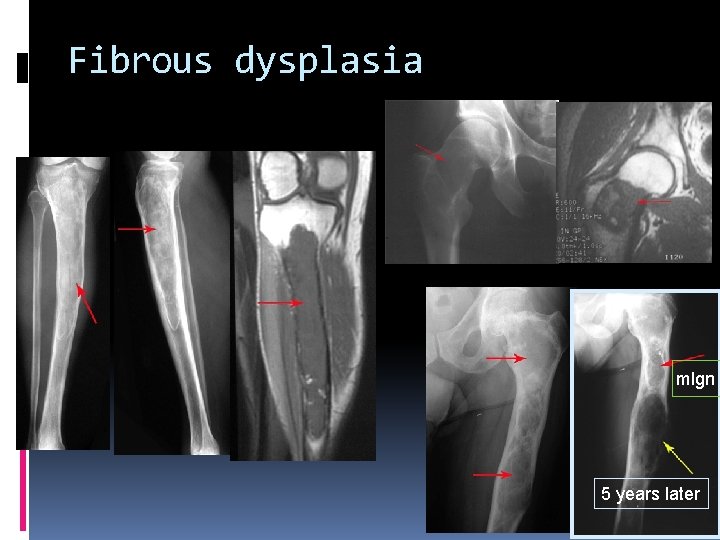

Fibrous dysplasia mlgn 5 years later